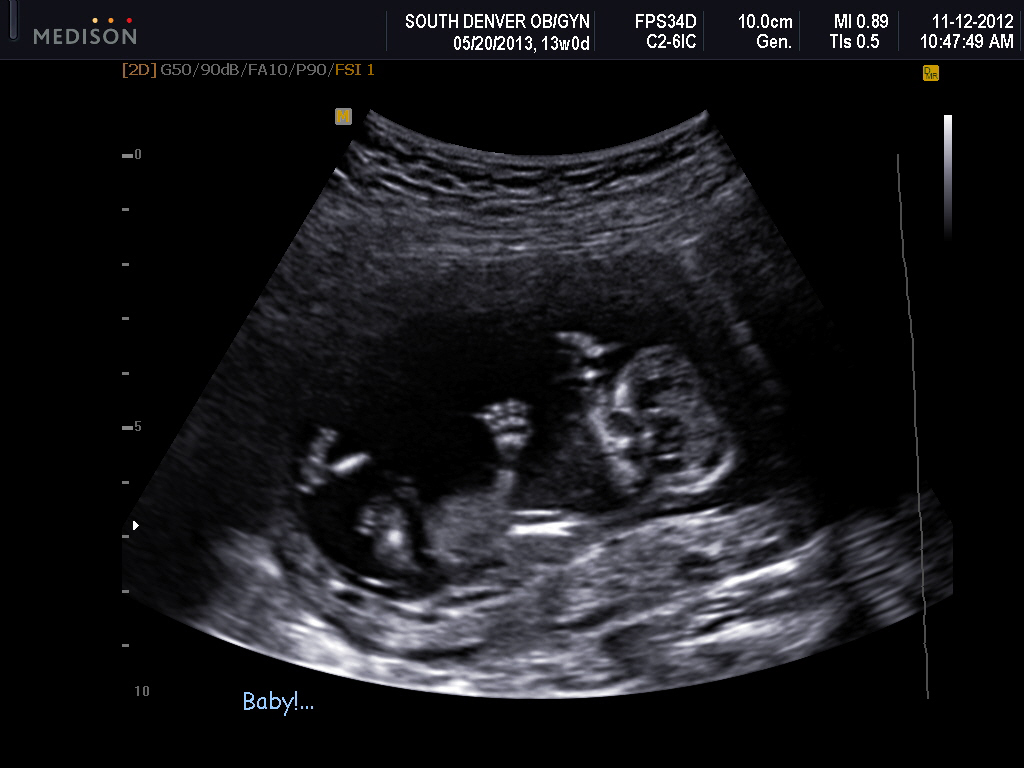

Attachment 6203Attachment 6204Attachment 6205

I had a video but not sure how to upload it. I had a potty shot on the video and I know they are not as accurate now but it sure looked like a boy. Does anybody know how to add a video?

I don't see any clues but I am very new to the nub theory. I love the image of your baby's hands. He/she looks like they are having a lot of fun in there.